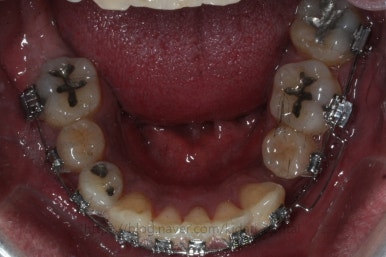

부산치아교정 키다리아저씨치과에 처음 내원 당시의 입안 모습입니다.

여러 가지 문제점이 있는데 하나씩 살펴볼게요.

치열이 많이 삐뚤하네요.

많이 삐뚠 상태에서 장기간 사용하다 보면 안좋은 방향으로 치아가 힘을 받게 되고 마모나 치아 목부분 패임이 심해집니다.

양치가 힘들어요. 양치가 힘들다 보니 세게 닦게 되고 치아 손상은 더 심해져요. 25세의 나이였는데 나이에 비해서 치아나이가 굉장히 많은거죠.

화살표 부분에 원래 송곳니가 있어야 되는데 보이질 않네요. 결손치아일 수도 있고 매복치아일 수도 있겠어요.

왼쪽 위 어금니도 한 개가 없어서 빈공간이 약간 남아있어요.

왼쪽 아래 작은 어금니는 아래쪽으로 많이 꺼져있네요.